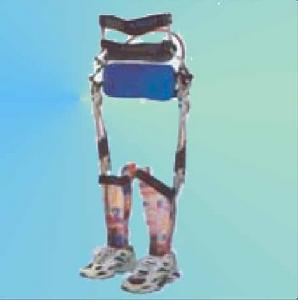

5、輔助器具:可以定做一些必要的支具來練習站立和步行,另外也可配備一些助行器等特殊工具,靠這些工具來補償功能的不足。